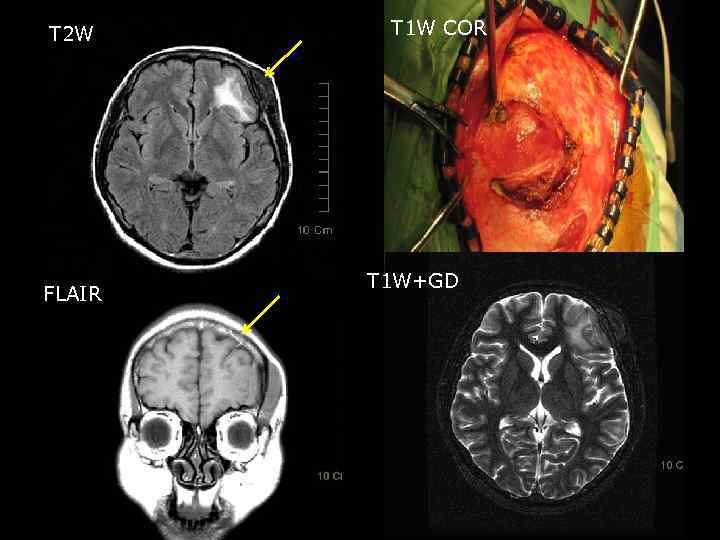

Клинический пример • Женщина 34 лет; • Жалобы на наличие опухолевидного образования в левой лобно-височной области в течение последних трех лет; • Объективное обследование: – Соматически компенсирована; – Психический статус без особенностей; – Общемозговой и менингиальной симптоматики нет; – Речевая продукция не нарушена; – Мышечный тонус не изменен; – Мышечная сила сохранена в полном объеме; – Чувствительных нарушений нет; – Статика и координация не нарушены Таким образом, очаговой симптоматики не выявлено 48

СКТ головного мозга 2 1 1. Опухоль левой лобно-височной области (менингиома) 2. Остеома лобной кости слева. 49

T 2 W FLAIR T 1 W COR T 1 W+GD 50